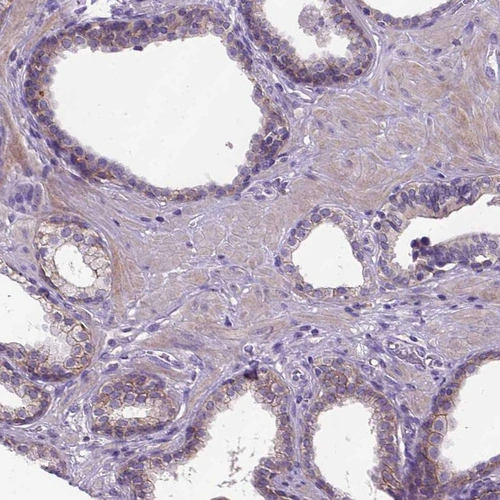

Immunohistochemistry analysis in human duodenum and cerebral cortex tissues using AMAb90865 antibody. Corresponding CDH1 RNA-seq data are presented for the same tissues.